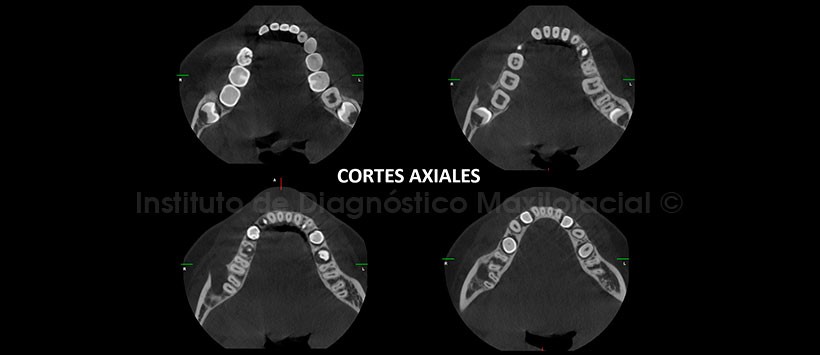

A la evaluación de la tomografía volumétrica (CBCT) en cortes axiales (Figura 2), transaxiales (Figura 3, 4) y tangenciales (Figura 5), se evidencia presencia de imagen hipodensa localizada a nivel de la cara vestibular de la pieza 4.7 que presenta las siguientes características: Bordes definidos, corticalizados, expande tabla ósea vestibular en aparente relación con la zona de furcación, de aproximadamente un 1cm de diámetro y 1cm3 de volumen (Figura 6).